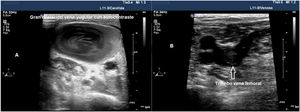

Ecocardiografía en el paciente en decúbito pronoUn gran porcentaje de pacientes con COVID-19 desarrollan SDRA con requerimiento de VM y maniobra de decúbito prono por IRA por largos periodos de tiempo. Durante estos periodos, muchos pacientes requieren un examen ecocardiográfico por diversas causas, sin embargo, movilizar al paciente a decúbito supino únicamente para esta prueba puede suponer un empeoramiento de su insuficiencia respiratoria. Las alternativas son la utilización de una sonda transesofágica o la realización de ecocardiografía transtorácica (ETT) en decúbito prono, para ello se debe colocar al paciente en posición de nadador con el miembro superior izquierdo estirado por encima de la cabeza. Se deberá elevar el hombro izquierdo colocando una almohada, colocando el transductor a nivel del quinto espacio intercostal izquierdo línea medioclavicular, para obtener todas las mediciones relacionadas al plano apical75 (fig. 6).